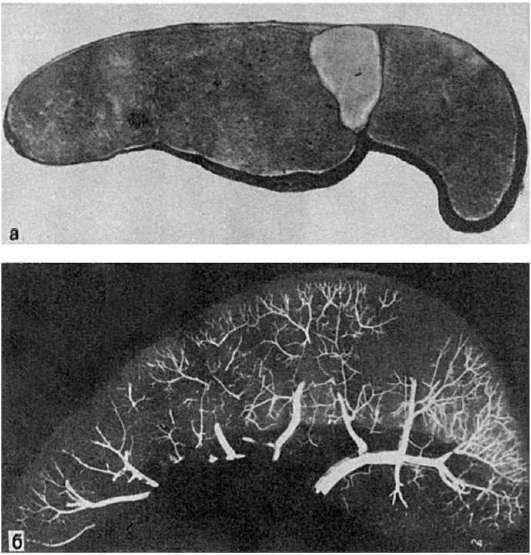

Форма, величина, цвет и консистенция инфаркта могут быть различными. Чаще инфаркты бываютклиновидными (рис. 46-49), основание клина обращено к капсуле, а острие - к воротам органа. Они образуются в селезенке, почках, легких, что определяется характером ангио-

Рис.

а - ишемический инфаркт в виде светлого треугольного участка, обращенного основанием к капсуле; б - ангиорентгенограмма той же селезенки. Отсутствие сосудов в области инфаркта

архитектоники этих органов - магистральным типом ветвления их артерий. Реже инфаркты имеютнеправильную форму (см. рис. 49). Такие инфаркты встречаются в сердце, мозге, кишечнике, т.е. в тех органах, где преобладает не магистральный, а рассыпной или смешанный тип ветвления артерий. Инфаркт может охватывать большую часть или весь орган (субтотальный или тотальный инфаркт) или обнаруживается лишь под микроскопом (микроинфаркт). Если инфаркт развивается по типу коагуляционного некроза, то ткань в области омертвения уплотняется, становится суховатой (инфаркт

Белый (ишемический) инфаркт представляет собой участок бело-желтого цвета, хорошо отграниченный от окружающей ткани (рис. 46). Обычно он возникает в участках с недостаточным коллатеральным кровообращением. Особенно часто встречается в селезенке, почках.